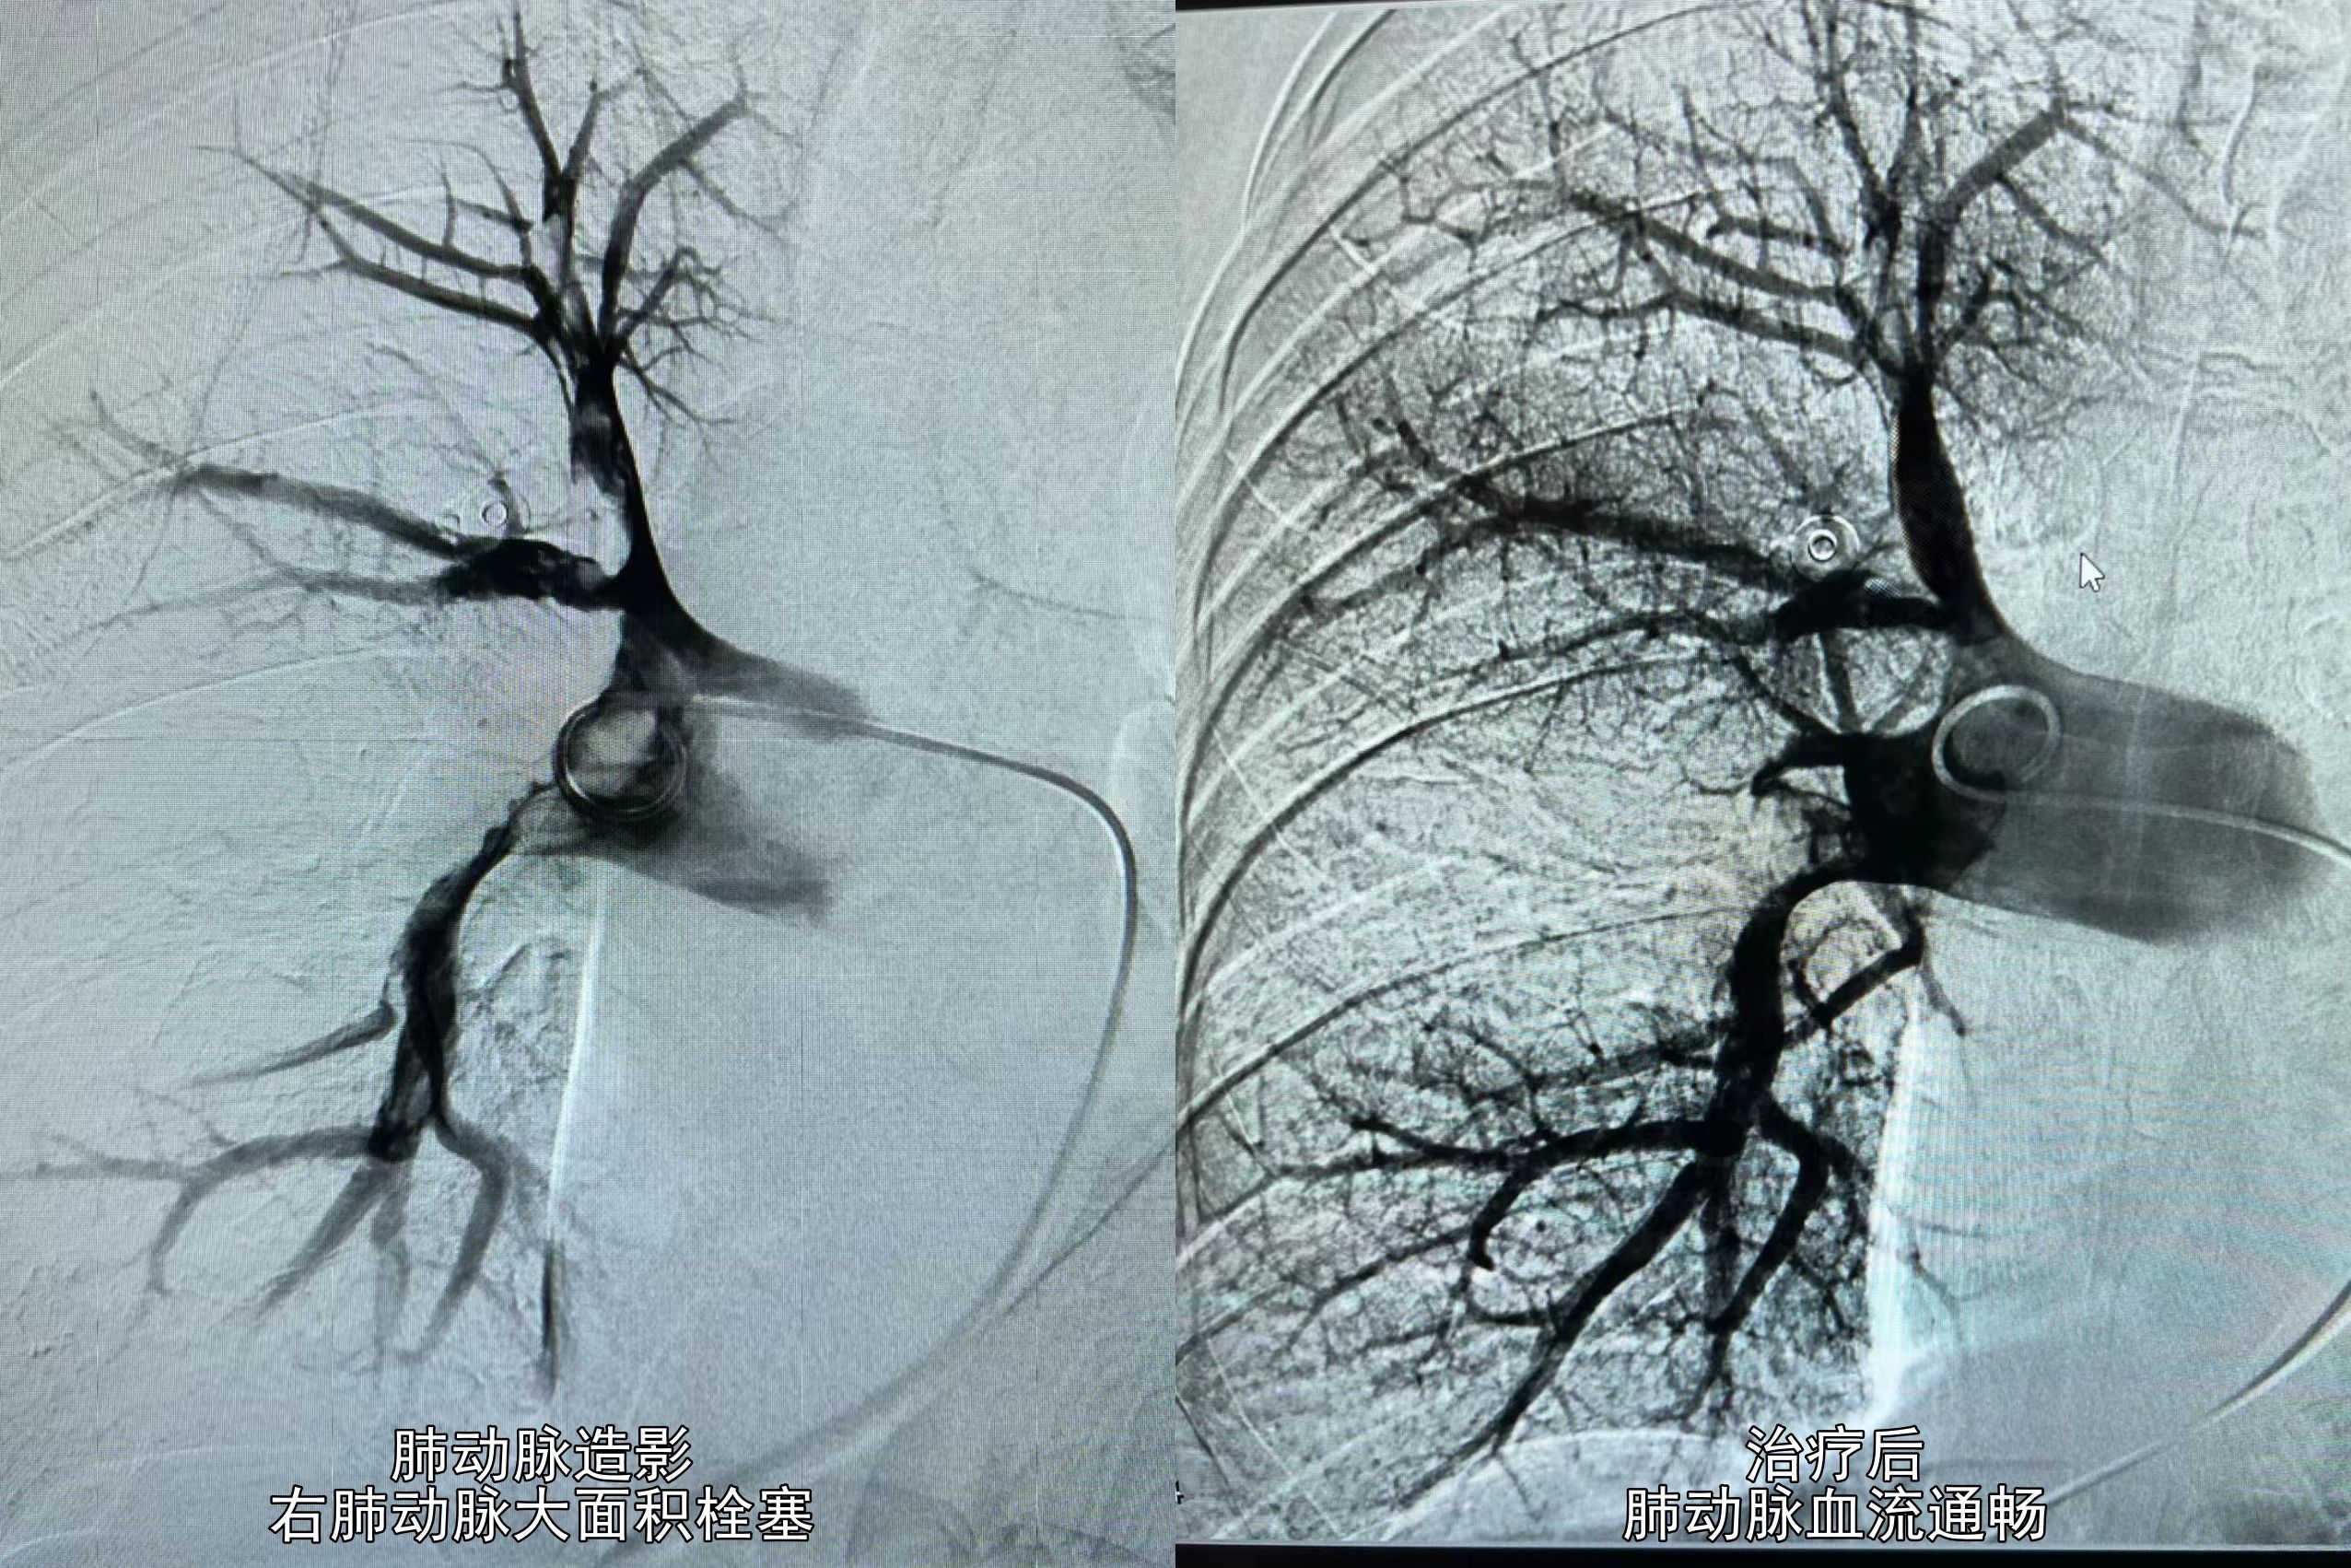

“通过介入导管进行肺动脉造影,显示右侧肺动脉主干见充盈缺损,肺动脉大面积栓塞。”据该院介入诊疗中心高斌主任介绍,考虑到肺动脉血栓较大、形成时间相对较长、栓塞十分紧密,术中对堵塞肺动脉的栓子进行精准碎栓,并用尿激酶进行腔内溶栓后,采用外周血栓抽吸导管抽出新鲜血栓数条,复查造影肺动脉血流通畅。综合前期诊断,为了防止下肢静脉血栓再次导致肺栓塞,在下腔静脉植入滤器1枚。

术前术后对比。

“栓子成功取出后,王爷爷胸闷症状立马好转,这就有了手术台上‘比耶、点赞’激动一幕。”高斌主任介绍,手术历时约90分钟,术中王爷爷生命体征平稳,术后血氧饱和度恢复到95%,原本青紫甲床很快恢复正常。